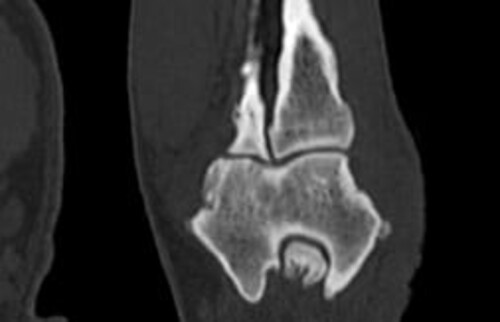

Nach der klinischen Diagnose werden die Hunde in unserer Klinik direkt im Computertomografen untersucht, sodass genau beurteilt werden kann, welche Gelenksanteile wie schwer betroffen sind, um eine individuelle Therapie festzulegen.

Schwarz-weiss Röntgenaufnahme